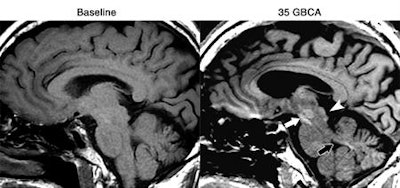

Patients who received more than 35 injections of gadolinium-based contrast agents (GBCAs) had higher levels of signal intensity on unenhanced MR images of the brain, according to a new study published online August 11 in Radiology. But researchers weren't able to find any adverse clinical effects in the individuals.

The group from Weill Cornell Medicine and Columbia University Medical Center found greater signal intensity in the dentate nucleus and global pallidus in patients who had a large number of gadolinium administrations, compared with individuals who had fewer GBCA administrations. Despite the rise in signal intensity, there were no obvious signs that the additional gadolinium caused any harm to patients.

All three radiologists found increased signal intensity in the dentate nucleus, globus pallidus, and substantia nigra in all 13 subjects, as well as greater signal intensity in regions such as the posterior thalamus, red nucleus, and colliculi in other subjects. The dentate nucleus also had the greatest mean increase in signal intensity, nearly double that of the globus pallidus and posterior thalamus.

The increase in signal intensity in the dentate nucleus was much more dramatic than what Kanda et al found in the same area, Prince and colleagues noted. The current research also differed from previous studies in discovering greater signal intensity in other brain regions.

"When there are more than 35 gadolinium injections, we are seeing more locations in the brain that show signal change beyond the dentate nucleus and global pallidus," Prince said.